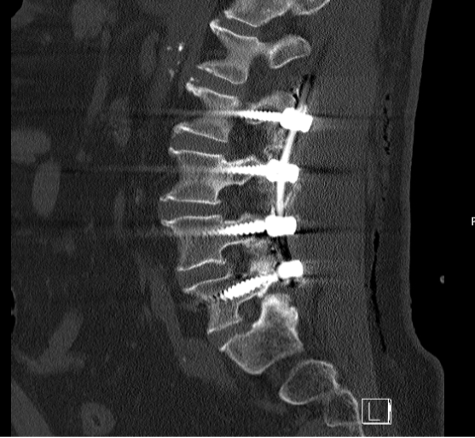

Üç yıl kadar önceki bu muayene ve tetkikler sonucunda Akın Bey, bana “henüz ameliyat safhasında değilsiniz, biraz daha fizik tedavi ve ağrı kesicilerle devam edelim” demişti. O günkü radyolojik tetkiklerde L4-L5 bölgesinde “lomber spinal stenoz” tabir edilen kanal daralmasından bahsediliyordu aslında. Bunun lomber dar kanal (spinal stenoz) ve buna eşlik eden spondilolistezis olduğu ifade edildi. Ben anlatması kolay olsun diye sinirlerin geçtiği omurga kanallarının daralması diyorum.

Ameliyatın bazı safhalarının video kaydını seyrettim daha sonra. Ne kadar hassas ve ince bir işlem olduğunu bir kere daha müşahede etmiş oldum. Omurgada milimetrenin küsurları bile önem kazanıyor. Oraya metallerin yerleştirilmesi büyük bir hassasiyet gerektiriyor. Akın Hoca bana ‘iğne ile kuyu kazmaya benzer bizim omurga üzerindeki işlemlerimiz’ demişti. O bakımdan doktorlar az da olsa bir endişe içinde ameliyatı sona erdiriyorlar ama ilk fırsatta bu metallerin yerli yerinde olup olmadığını ve omurga kanallarındaki daralmanın giderilip giderilmediğini görmek istiyorlar. Bu sebeple beni sabah saat 05.30’da gelip tomografiye götürdüler ve ortaya çıkan neticeyi görmek istediler. Daha sonra odama gelen Dr. Akın Bey ve arkadaşları yerleştirilen metal parçacıklarının tam istedikleri konumda olduğunu gördüklerini söylediler ve beni rahatlattılar. Şu anda omurgamda dört adet bir tarafta, dört adet diğer tarafta olmak üzere sekiz metal parçası taşıyorum. Yani omurgama yerleştirilen vidalar ve sabitleyici metal çubuklarla geziyorum.

Ameliyatın üzerinden iki buçuk ay geçtikten sonra Dr Akın Hocaya gittim kontrol için. Yeniden tomografi çekildi. Hoca, her şey yolunda dedi ama beni kemik erimesi kaygısıyla başka bir uzmana yönlendirdi. ‘Bu bir tedbirdir’ diye de vurguladı. Şimdi onun neticelerine de bakarak korseyi daha ne kadar taşımam gerektiğine karar verecek.